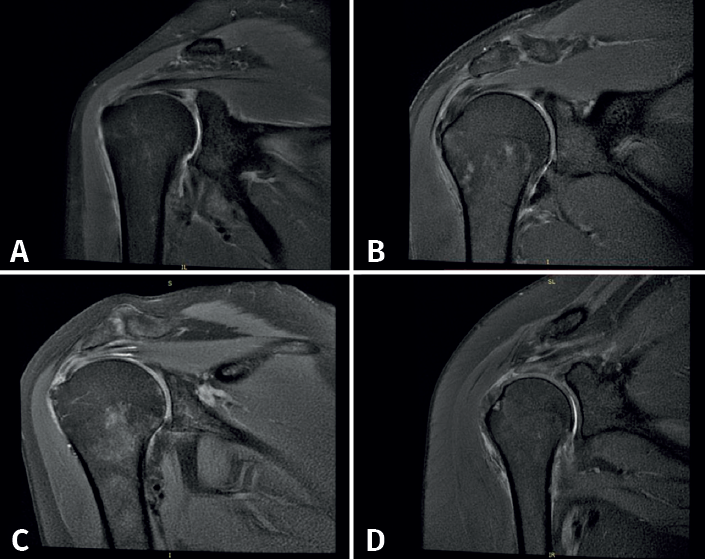

Los criterios diagnósticos para la patología del MR por RM incluyeron: 1) tendinopatía: definida como un aumento de la intensidad de la señal en imágenes ponderadas de densidad de protones (DP) pero no tan brillantes como la señal en secuencia T2; 2) rotura parcial: definida como el aumento focal de la intensidad de la señal por disrupción de fibras en secuencia T1, en imágenes DP y en T2; 3) rotura parcial del espesor completo: con las mismas consideraciones que la anterior pero que afecta el espesor completo tendinoso. Adicionalmente, se evaluó el labrum, donde las lesiones se observan en secuencia T1 y T2, y lesiones de la articulación glenohumeral y acromioclavicular observadas en T2 med (Figura 1)(6).